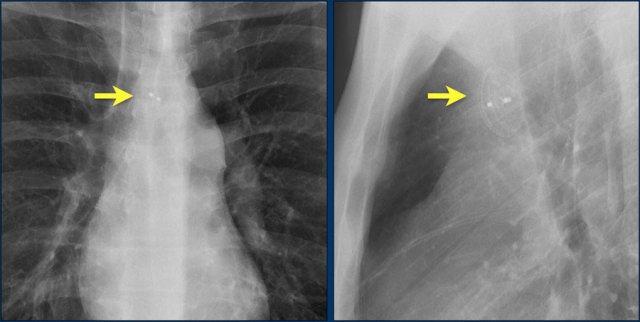

Hình ảnh được chụp ngay sau khi đặt ICD.

Có hình ảnh tràn khí màng phổi nhỏ (mũi tên).

Đây là biến chứng thường gặp nhất.